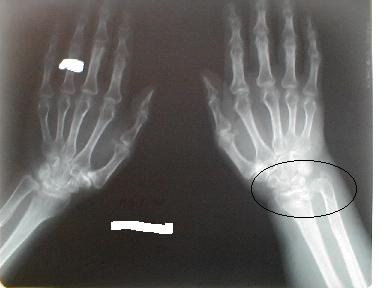

2月3日正面像

側面像